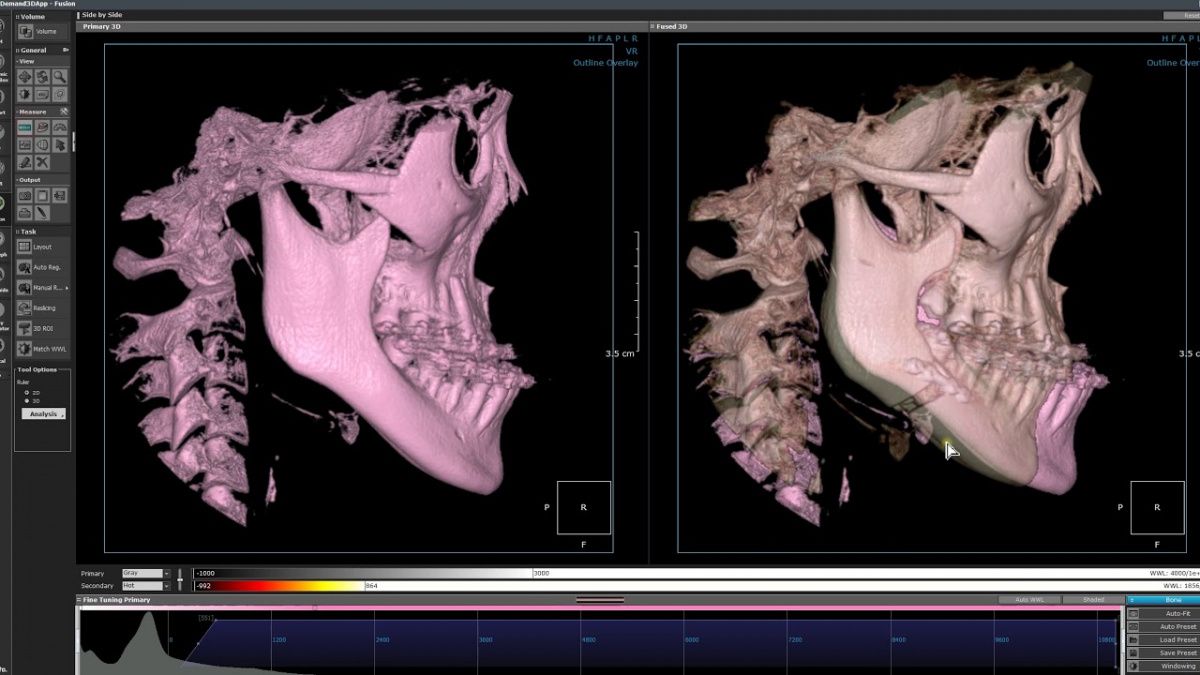

• 3D режим – показывает трехмерную модель челюсти с целью определения аномалий, деформация, а также визуализации виртуальных имплантатов.

Таким образом обе программы являются простыми в пользовании, но обладающими обширным спектром возможностей для диагностики любыми специалистами-стоматологами. В данные программы происходит загрузка классических файлов DICOM 3.0, которые являются общепринятым форматом записи данных пациента. Это важный момент, так как позволяют врачу, имеющему полную версию программы загружать даже сторонние исследования и просматривать их в этих программах. Простота в освоении этих программ позволяет даже специалисту, не работающему раннее с этими программами, быстро адаптироваться и получить качественную информацию. Возможность выгрузки STL-файла дополнительно создает возможность интегрировать данные с цифровым ортопедическим протоколом.